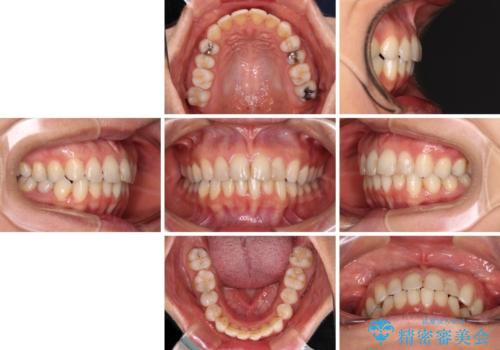

- 前歯のデコボコを気にして来院された患者様です。

IPR(歯と歯の間を削る)によってデコボコが解消するように設計し、インビザラインにより治療を行うこととしました。

下顎善の叢生をもう少し改善したかったのですが、患者様は十分に整ったとのことで治療を終えることになりました。